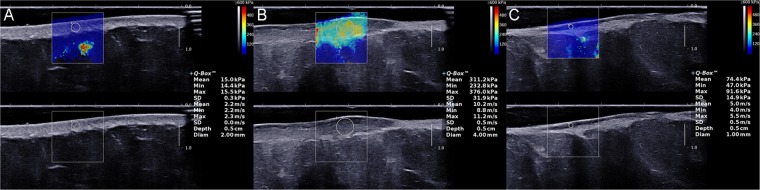

SWE examination was undertaken by a trained sonographer using Aixplorer US system (SuperSonic Imaging, Aix-en-Provence, France) with a SL 15–4 linear probe operating at 4–15 MHz (central frequency: 7.5 MHz). And the superficial musculoskeletal mode was preset. The precautions of manipulating the probe were as same as when acquiring a B-mode image by using another device. After switching to SWE-mode, the operator maintained the transducer for few seconds to obtain a stable color-coded SWE image. Ultrasound gel covering on the probe tip was proven not to influence the appearance of the elastogram16,26. The square region of interest, which was marked on targeted skin area, was used to collect SWE data. Colors, as shown in the ROI, varied along with the changing the skin stiffness. A very soft tissue was coded by dark blue and a very hard lesion was coded by red, while other colors (light blue, green, and orange) represented the increase of stiffness of tissue between very soft tissue and very hard lesion. After acquisition of a stable color-coded square ROI, skin elasticity was measured in a small round area called Q-box, which was put in the middle of the ROI. The diameter of Q-box varied due to the size of targeted zone. A series of the elastic moduli, including the mean, maximum, minimum, and standard deviation for values of both Young’s modulus and shear wave velocity were calculated by the system and exhibited on the right side of the screen automatically. Figure 3 exhibits three standard elastograpy images of normal skin (A), and keloid in untreated condition (B) and treated condition (C), which were collected from one patient who was accepted intralesional steriods injection. Three measurements, which meant three Q-boxes in three images, were performed at each site. The mean values of Young’s modulus and shear wave velocity were selected as representative values for each obtained image in this study. Additionally, the averaged mean Young’s modulus value (E-mean) and the averaged mean shear wave velocity value (C-mean) were presented as kPa and m/s, respectively.

Figure 3.

Elastography images of normal skin (A), and keloid in untreated condition (B) and treated condition (C). The post-treated keloid was accepted intralesional steriods injection and all images were collected from the same patient as in Fig. 2. The selected quantitative values, including the mean values of Young’s modulus and shear wave velocity were automatically displayed on the image. The decrease of the two values after therapy is clearly visible.